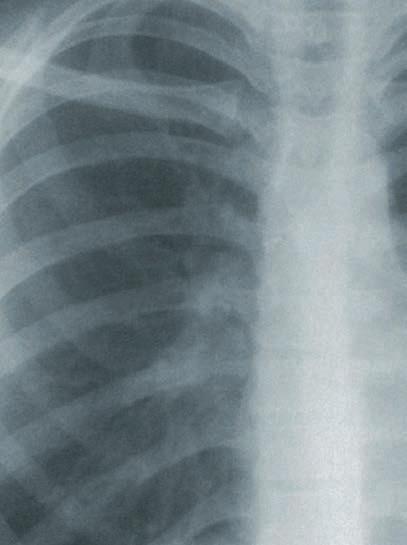

DIE ABNAHME DES ATEMVOLUMENS STOPPEN

MANCHE LUNGENFIBROSEN FÜHREN SCHNELLER ZUM TOD ALS DIE MEISTEN KREBSARTEN. AUCH WENN IHRE HÄUFIGKEIT ZUNIMMT, SIND ES SELTENE KRANKHEITEN. DAS MACHT DIE KLINISCHE ERFORSCHUNG NEUER MEDIKAMENTE ZU EINER BESONDEREN HERAUSFORDERUNG – AUCH FÜR PROFESSOR ANDREAS GÜNTHER AM DEUTSCHEN ZENTRUM FÜR LUNGENFORSCHUNG (DZL). #2|202212 L UNGENFORSCHUNG LICHTBLICK

ach dich nicht verrückt“, riet der Hausarzt seinem Bekannten. Der musste beim Berg steigen, das ihn auch als über 60-Jährigen noch auf Viertausender führte, immer häu figer um Luft ringen. „Deine Lunge funktio niert gut, das hat der Facharzt bestätigt.“ Der Patient bestand trotzdem auf einer Über weisung zum Chirurgen, um der Sache durch eine Lungenbiopsie auf den Grund gehen zu lassen. Und leider zeigte die Gewebeprobe das typische Muster einer idiopathischen pulmonalen Fibrose (IPF). Das hauchdünne Bindegewebe in den äußersten Verzweigun gen des Lungenbaums erschien stellenweise wie mit dem Stift nachgezogen und zu Ho nigwaben verformt. Dort, wo ihm frischer Sauerstoff zuströmt und es sich stützend um Lungenbläschen und Blutgefäße schlingt.

Idiopathisch heißt: Ursache unbekannt. Das ist bei der Hälfte aller Lungenfibrosen der Fall. Vor allem ältere Männer erkranken daran. Ihre Lunge vernarbt und verhär tet, sie spüren einen zunehmend heftigen Widerstand beim Luftholen, die Kapazität ihrer Lunge nimmt kontinuierlich ab. „Wer sportlich aktiv ist, bemerkt das früher als Menschen, die sich so wenig bewegen, dass ihnen die Abnahme ihrer Lungenreserven

nicht auffällt“, sagt Professor Günther. Die Lungen funktion des Bergsteigers zum Beispiel sei nach der Diagnose zehn Jahre lang nur allmählich abgefallen. Erst nach einer schweren Atemwegsinfektion habe sie sich rapide verschlechtert. „Für viele Patientinnen und Patienten ist eine solche Infektion aber erst das Schlüsselereignis, das sie zum Doktor treibt.“ Nicht selten kämen sie dann nach Luft hechelnd und von einem quälenden Reizhusten geplagt mit einer schon mehr als halbierten Lungenkapazität in die Ambulanz. „Diese Patientinnen und Patienten haben nach der Diagnose einer IPF nicht mehr lange zu leben“, sagt Günther. „Ihre Prognose ist schlechter als bei den meisten Krebserkrankungen.“

Ein gesunder Mensch kann nach einer sehr tiefen Einatmung etwa drei bis viereinhalb Liter Luft ausatmen. Diese so genannte forcierte Vitalkapazität nimmt bei Fibrose-Patientinnen und -Patienten stark ab: Sie verlieren pro Jahr rund 100 bis 150 Milliliter dieses Volumens.

Zur Erleichterung vieler Ärztinnen und Ärzte sowie Patientinnen und Patienten wurden zwischen 2011 und 2015 auf der Basis großer klinischer Studien zu nächst in Europa und dann in den USA zwei Medi kamente zugelassen, die speziell zur Behandlung der IPF entwickelt worden waren. Beide hemmen eine Reihe molekularer Botenstoffe, die dem Bindegewe be der Lunge befehlen zu wachsen. Beide können das Fortschreiten der Vernarbung zwar nicht stoppen, aber verlangsamen. Die Maßzahl dafür ist die forcierte Vitalkapazität (FVC). Sie gibt an, wieviel Liter Luft ein Mensch nach einer sehr tiefen Einatmung mit voller Kraft ausatmen kann. Beim gesunden Erwach senen sind das je nach Alter, Größe und Geschlecht drei bis viereinhalb Liter. „IPF-Patienten verlieren 100 bis 150 Milliliter dieses Volumens pro Jahr“, sagt Günther. „Die beiden antifibrotischen Medikamente Pirfenidon und Nintedanib sind etwa gleich wirksam. Sie verringern diesen Verlust um 50 Prozent.“ Das klinge in absoluten Zahlen nach einem nur kleinen Luftgewinn, bedeute aber: „IPF-Patienten, die mit ei nem dieser Medikamente behandelt werden, leben doppelt so lang.“